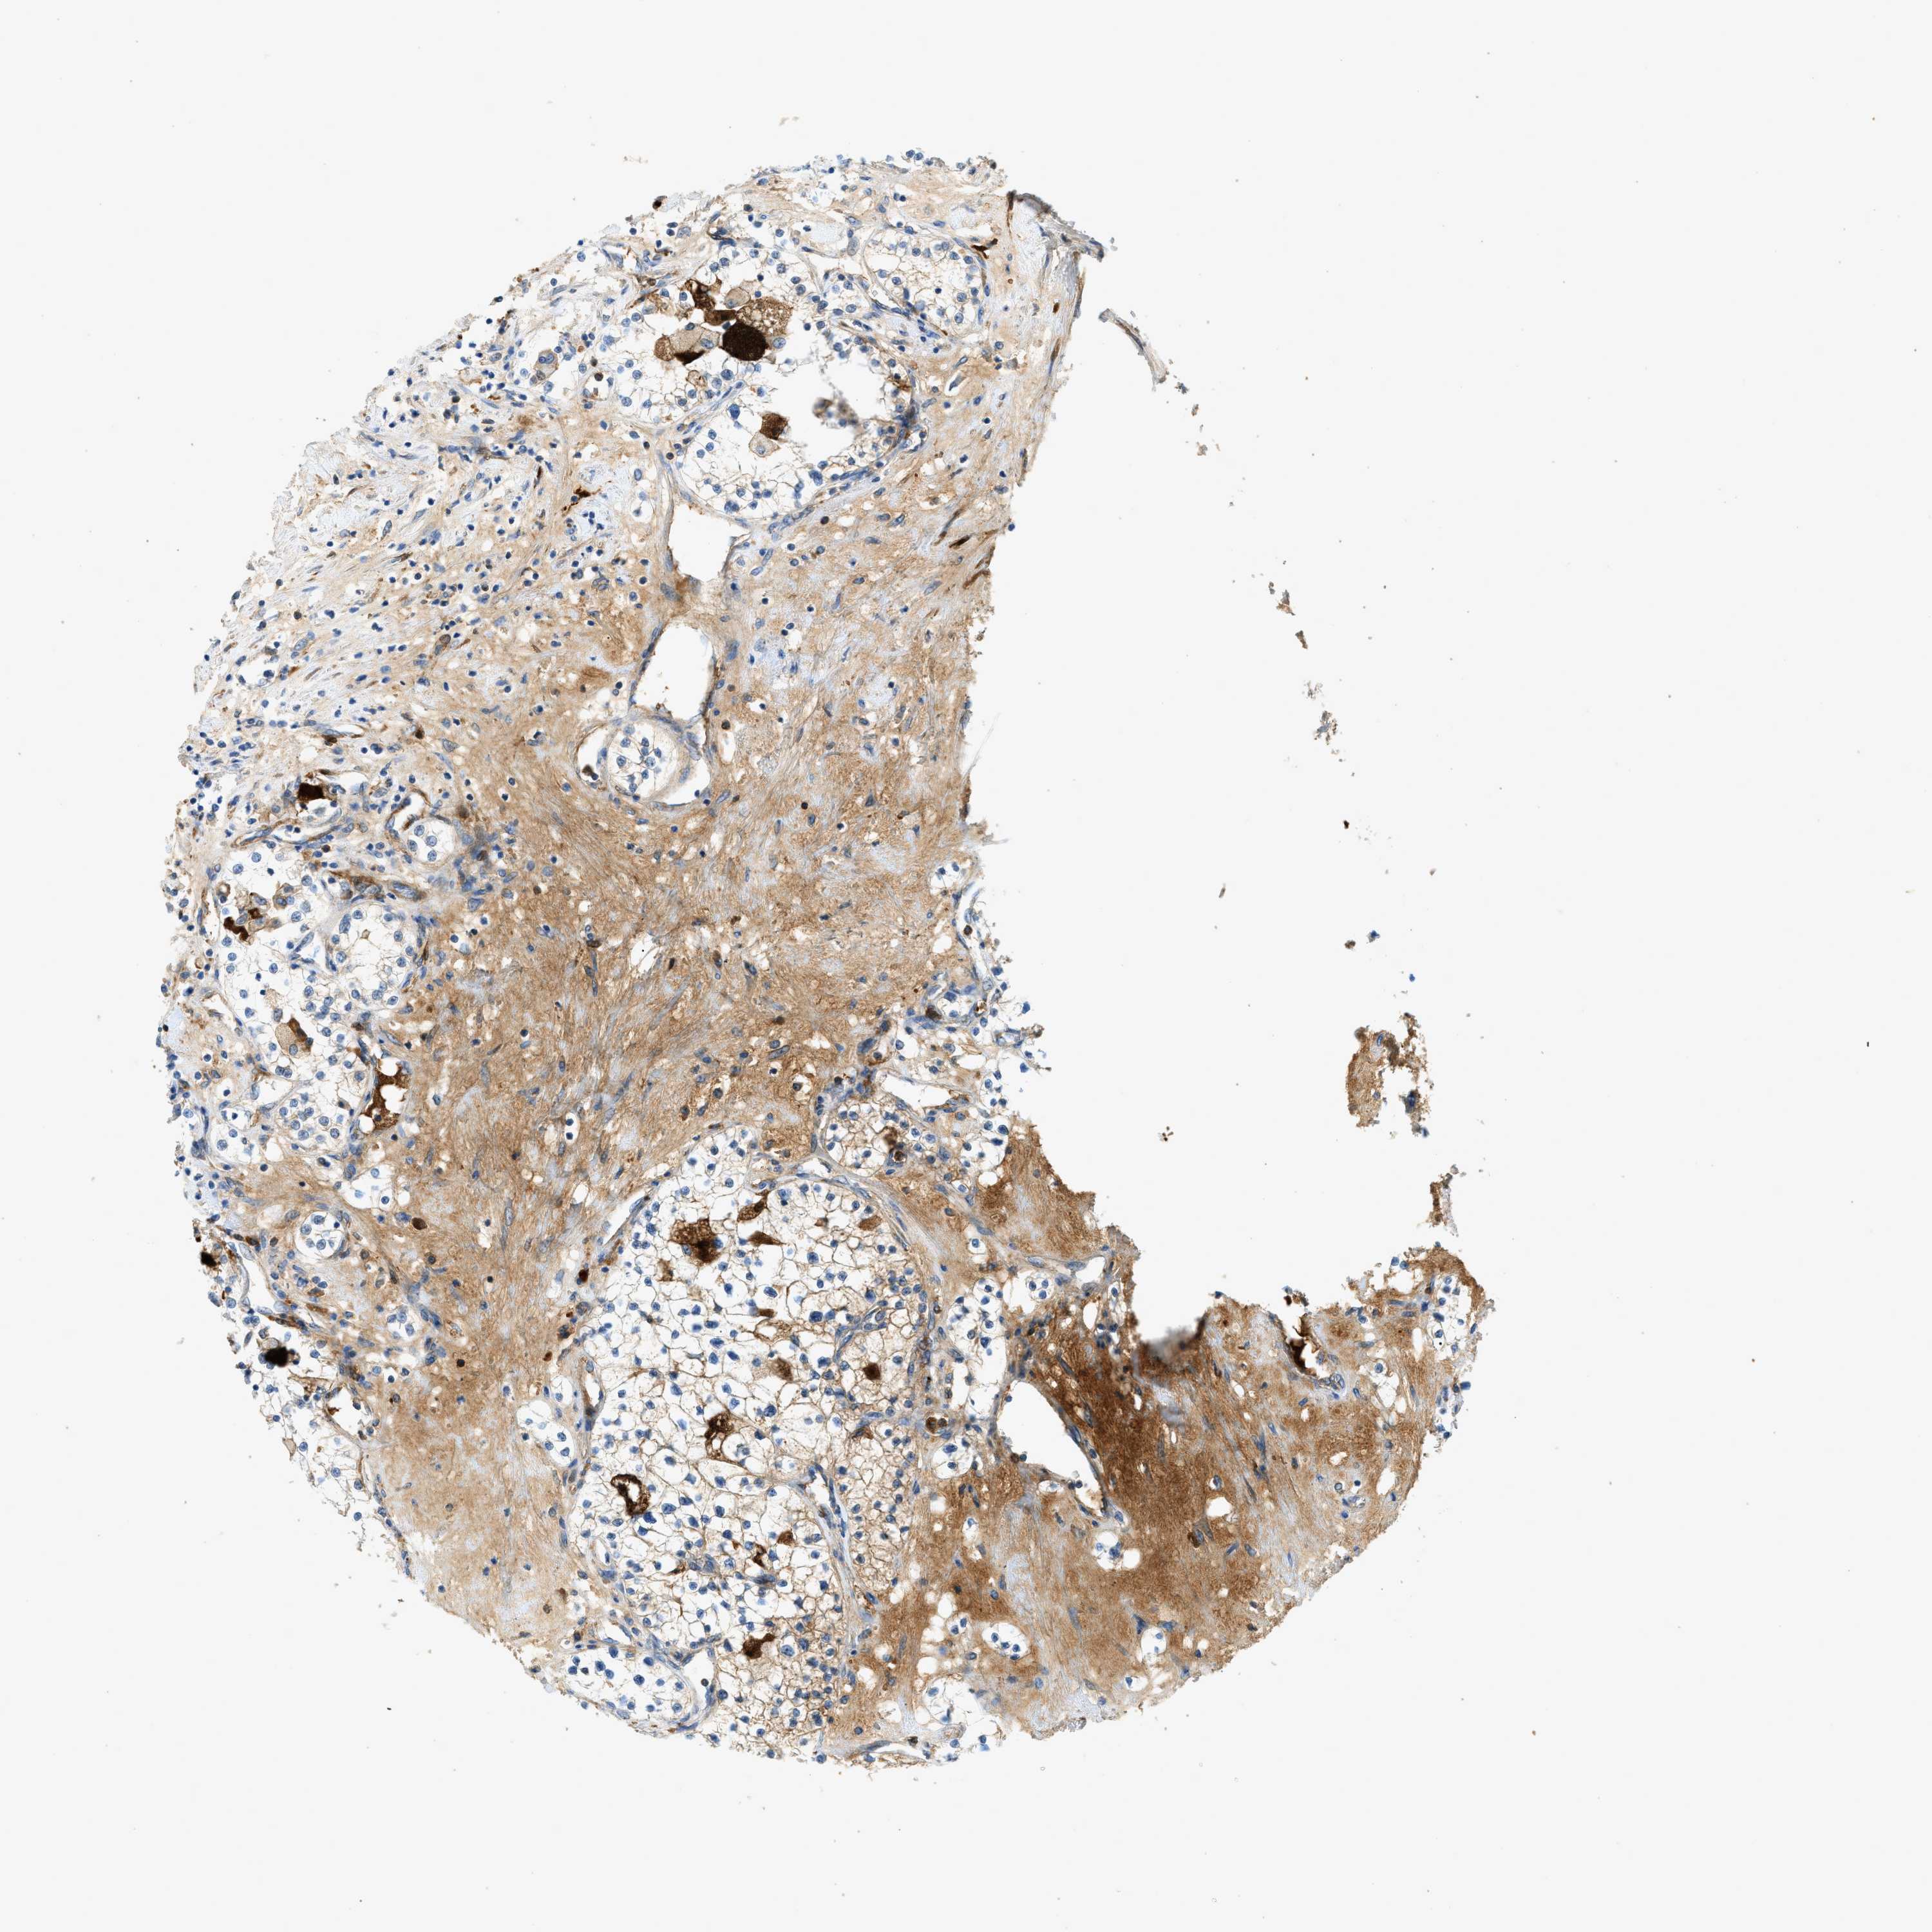

KIDNEY RENAL PAPILLARY CELL CARCINOMA (TCGA) - Interactive survival scatter ploti

The Survival Scatter plot shows the clinical status (i.e. dead or alive) for all individuals in the patient cohort, based on the same data that underlies the corresponding Kaplan-Meier plots. Patients that are alive at last time for follow-up are shown in blue and patients who have died during the study are shown in red.

The x-axis shows the expression levels (FPKM) of the investigated gene in the tumor tissue at the time of diagnosis. The y-axis shows the follow-up time after diagnosis (years). Both axes are complimented with kernel density curves demonstrating the data density over the axes. The top density plot shows the expression levels (FPKM) distribution among dead (red) and alive patients (blue). The right density plot shows the data density of the survived years of dead patients with high and low expression levels respectively, stratified using the cutoff indicated by the vertical dashed line through the Survival Scatter plot. This cutoff is automatically defined based on the FPKM cutoff that minimizes the p-score. The cutoff can be changed by dragging the vertical line or by entering a cutoff value in the square labeled "Current cut-off".

Under the Survival Scatter plot the p-score landscape (black curve; left axis) is shown together with dead median separation (red curve; right axis). Dead median separation is the difference in median mRNA expression between patients who have died with high and low expression, respectively. It is calculated as follows: median FPKM expression of dead patients with high expression - median FPKM expression of dead patients with low expression. This is intended to aid the user in visually exploring custom cutoffs and the associated p-scores and dead median separation.

Individual patient data is displayed and can be filtered by clicking on one or more of the category buttons on the top of the page. Categories describing expression level and patient information include: high, low, alive, dead, female, male and tumor stages. The scale of the x-axis can be toggled between linear and log-scale by clicking on the "x log" button. Mouse-over function shows TCGA ID, patient information and mRNA expression (FPKM) for each patient.

& Survival analysisi

Kaplan-Meier plots summarize results from analysis of correlation between mRNA expression level and patient survival. Patients were divided based on level of expression into one of the two groups "low" (under cut off) or "high" (over cut off). X-axis shows time for survival (years) and y-axis shows the probability of survival, where 1.0 corresponds to 100 percent.

F2 is not prognostic in Kidney Renal Papillary Cell Carcinoma (TCGA)

Best expression cut offi

: N/A

TCGA RNA samplesi

RNA-seq data is reported as average FPKM (number Fragments Per Kilobase of exon per Million reads), generated by the The Cancer Genome Atlas (TCGA) .

Normal distribution across the dataset is visualized with box plots, shown as median and 25th and 75th percentiles. Points are displayed as outliers if they are above or below 1.5 times the interquartile range. FPKM values of the individual samples are presented next to the box plot.

Average pTPM 0.3

Number of samples 282